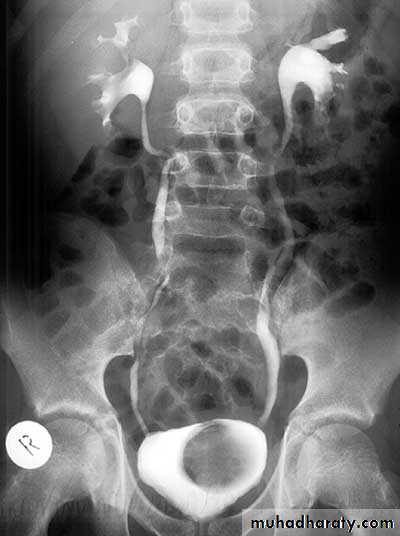

Duplication of the renal system

Horse shoe kidney

Crossed ectopia